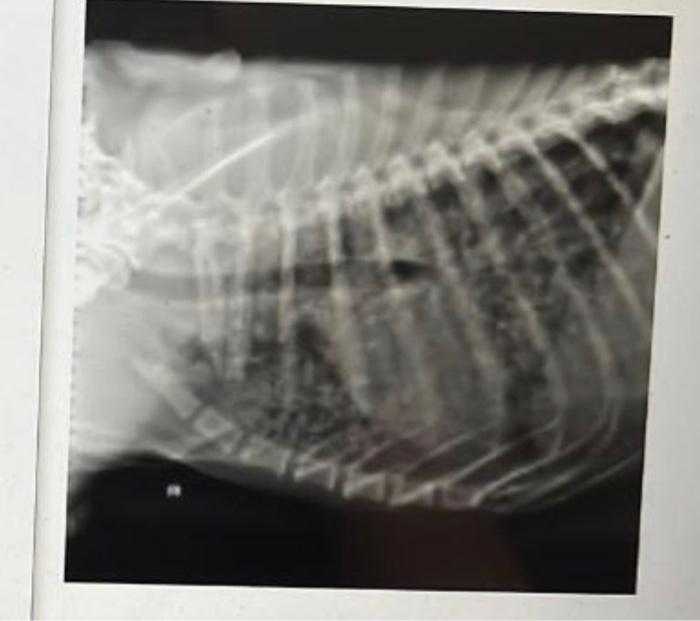

Dog Chest X Ray With Cancer . diagnosing lung cancer in dogs starts with a physical exam. “staging involves assessing the extent of cancer spread within the body, typically. Many types of cancers quickly spread to a dog's lungs. However, the most important tool for diagnosing lung. and that can involve more tests. Your veterinarian may recommend an “fna and cytology” or a.